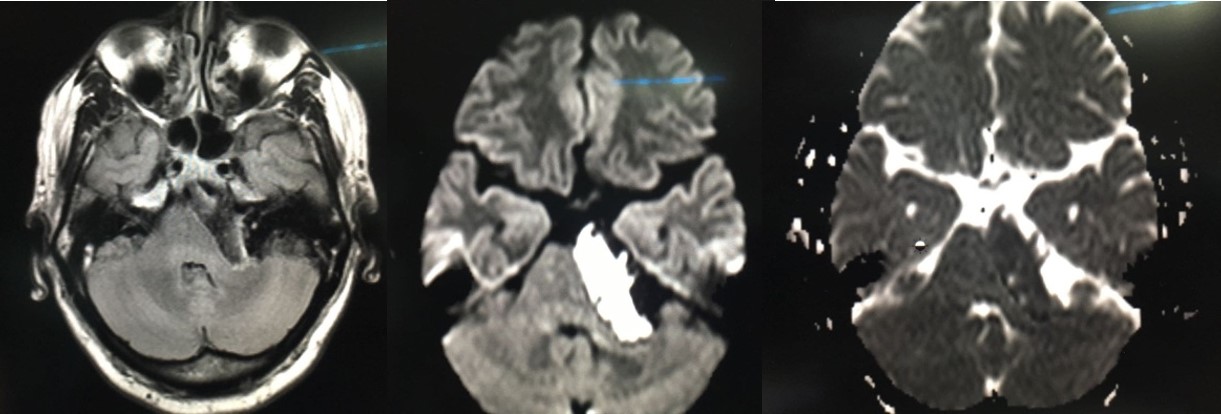

Question: 50yrs lady presented with gradual onset ataxia and left ear hearing loss. MRI is shown below. The likely diagnosis is:

Correct Answer: Epidermoid cyst

Explaination: Epidermoids are often indistinguishable fromarachnoid cystsor dilated CSF spaces on many MR sequences, except for DWI/ADC which helps to differentiate them<br>T1 usually isointense to CSF<br>T1 C+(Gd) thin enhancement around the periphery may sometimes be seen<br>T2 usually isointense to CSF (65%)<br>FLAIR often heterogeneousdirty signal higher than CSF<br>DWI/ADC: very bright on DWI<br>- similar ADC values compared to adjacent brain parenchyma<br>- useful for differentiation from arachnoid cysts due to increased signal (due to a combination of abnormal restricted diffusion andT2 shine through), which is not seen with arachnoid cysts